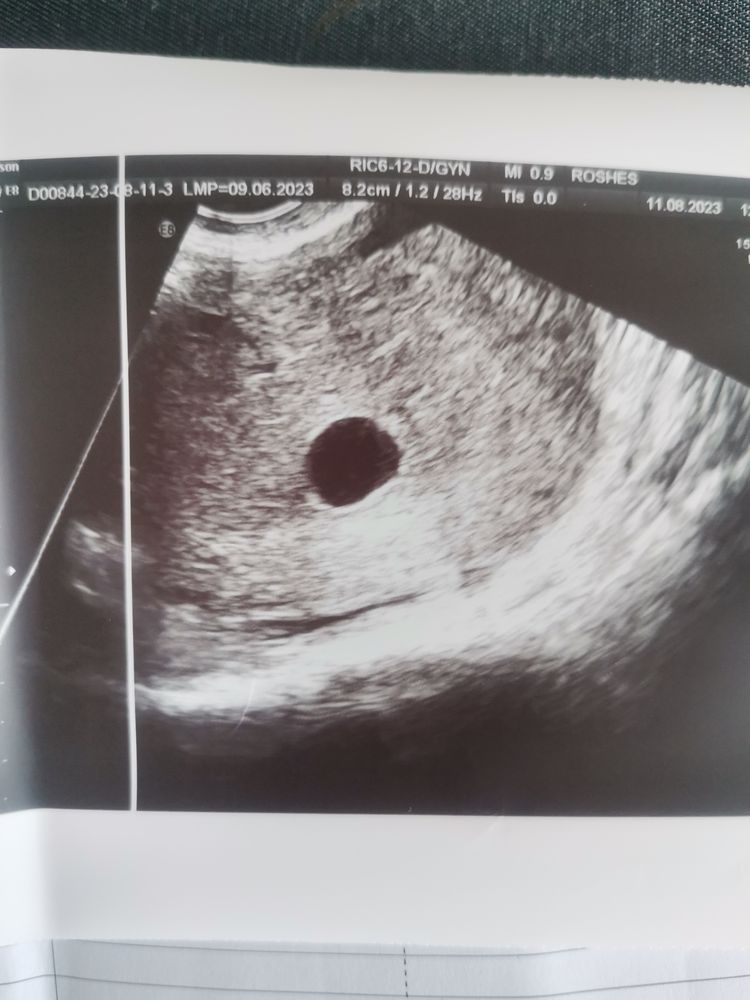

9 недель акушерский срок, пя 13 мм, за неделю выросло на 3 мм, врач говорит еще неделю подождать, чего ждать? Мне и так плохо! Эмбриона нет, ЖМ нет, это конец, плачу, не могу остановиться... У кого такое было, как переживали? Самое интересное, что ни выделений, ни болей, только грудь и тошнит, но всё пусто, его нет, лучше бы уже само вышло😭😭😭😭😭😭

Арина, у меня неделю назад было 10 мм, слишком медленно растет( шансов нет(((

Анастасия Михалевич, СВДЯ 10 мм это 5.6 нед, у вас разница выходит 3 дня. А сколько хгч? Знаете, анэмбрионию по УЗИ ставят при СВДЯ больше 20-25 мм! Вот если 25 мм, а эмбриона нет, это шансов нет.

Другое дело у вас должен уже быть желточный мешочек! В вашем случае подозрение на анэмбрионию есть. Ждите, в норме при СВДЯ 16 мм должен появиться эмбрион. И желточный мешочек тоже.